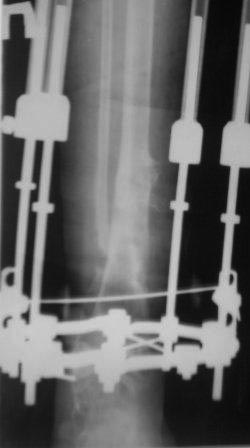

Контрольная Р-грамма на аппарате Илизарова после дистракции, теперь видимо придется стабилизировать аппарат после устранения остаточных деформаций.

С увважением Абдурашид.